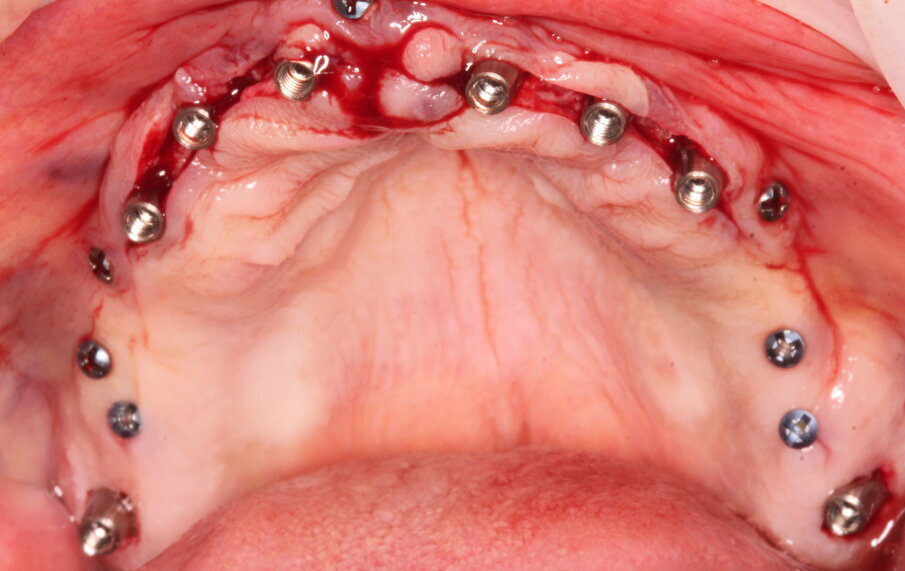

Gli impianti vengono distribuiti lungo tutta l’arcata cercando il parallelismo e limitando il più possibile i cantilever (6-7 impianti superiori e 5-6 impianti inferiori). La scelta di utilizzare i monconi dritti (grazie al parallelismo degli impianti) è da preferire in quanto quest’ultimi sono anche i più robusti e resistenti nel tempo al carico assiale; inoltre caricano l’impianto lungo il suo asse limitando i carichi disassati. Una volta elevato il lembo mucoperiosteo ed evidenziato l’osso alveolare o basale, attenzione deve essere fatta nel fare un’ostectomia riduttiva mediante una fresa a palla del diametro di 0,6-0,8 cm per creare un piano più uniforme possibile tale da formare una piattaforma d’osso alla stessa altezza, guadagnando anche spessore V-L ed uniformità. Gli impianti devono essere posizionati alla stessa altezza tra di loro e distanziati in maniera tale da favorire le manovre di igiene orale inter-implantare. Una volta posizionate le fixture sottocrestali (1-3 mm) come descritto, vanno connessi i monconi solitamente con collare mucoso di 3-4,5 mm in altezza, ponendo particolare attenzione che i tessuti molli suturati non coprano la parte di accoppiamento conometrico. Verificato il parallelismo corretto dei monconi mediante i pin parallelizzatori, siamo certi che l’accoppiamento e la disconnessione delle cappette contenute nella protesi potrà avvenire nel miglior modo possibile senza creare tensioni.

Un’impronta in silicone o digitale sulle cappette in situ accoppiate va presa alla fine della chirurgia, una volta suturati i lembi. Il paziente lascia lo studio con delle cappette provvisorie in Peek a protezione dei monconi e con la sua protesi riadattata oppure con una stampata del Brega riempita con impacco parodontale come medicamento.